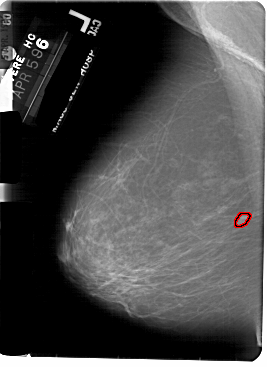

A_1855_1.LEFT_MLO

LEFT_MLO LINES 5491 PIXELS_PER_LINE 3991 BITS_PER_PIXEL 12 RESOLUTION 43.5 OVERLAY

FILE: A_1855_1.LEFT_MLO.OVERLAY

TOTAL_ABNORMALITIES 1

ABNORMALITY 1

LESION_TYPE MASS SHAPE OVAL MARGINS OBSCURED

ASSESSMENT 3

SUBTLETY 3

PATHOLOGY BENIGN

TOTAL_OUTLINES 1

BOUNDARY